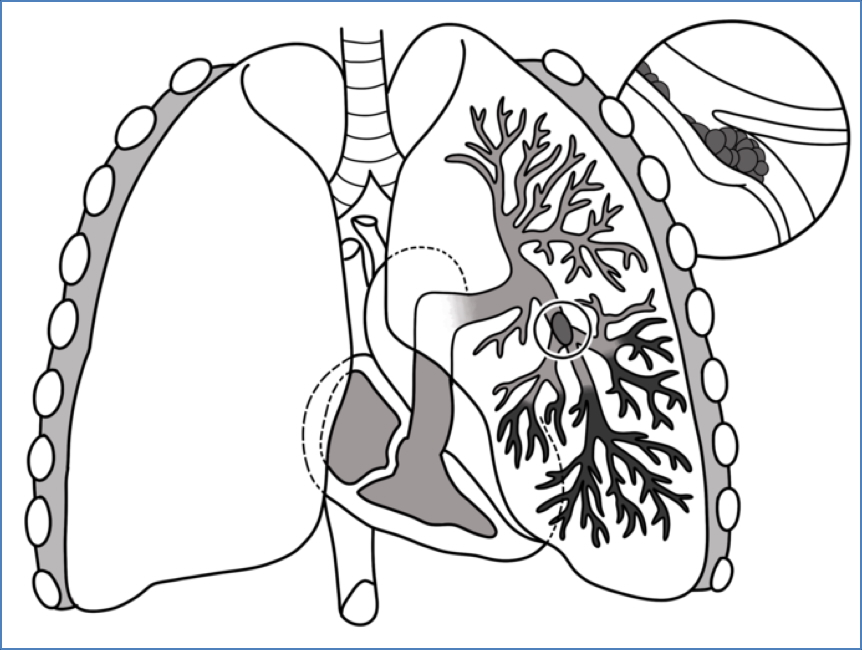

Pulmonary Embolism

- Foreign material obstructing a pulmonary vessel.

- Most commonly blood clot (thrombus).

- Prevents oxygenation of blood in affected region.